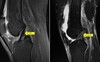

MRI and CT

MRI : Great for soft tissue and bone changes (infection, inflammation, necrosis, etc); taken in slices like CT; can be distorted by metal

CT : Great for seeing bone and alignment issues in multiple slices; can result in 3-D reconstruction; not great for soft tissue